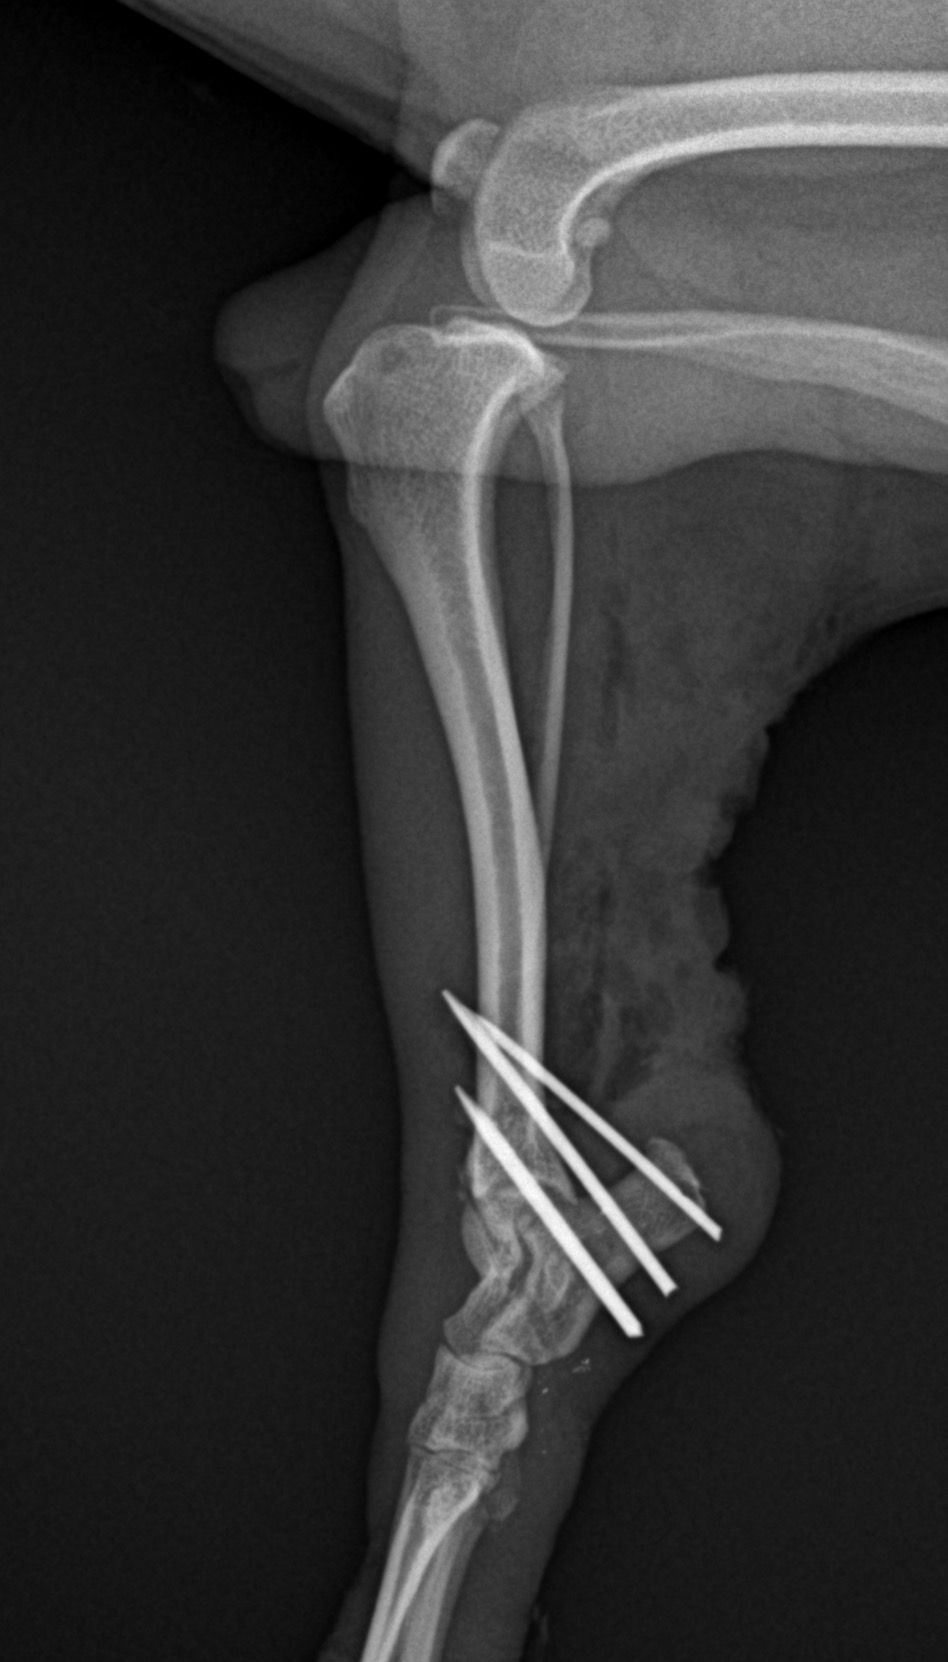

アキレス腱断裂 主治医よりアキレス腱断裂した患者さんが脚を着けなくなったので、なんとかして欲しいと連絡がありました。経関節ピンによる一時的な足根関節の仮固定とアキレス腱の縫合術により対応しました。しばらくは安静が必要です。 症例カテゴリー 放射線治療整形外科軟部組織外科脳神経外科内科腫瘍外科救急・集中治療リハビリテーション科腫瘍内科内視鏡科脳神経科呼吸器外科中医・漢方猫の腎移植循環器科